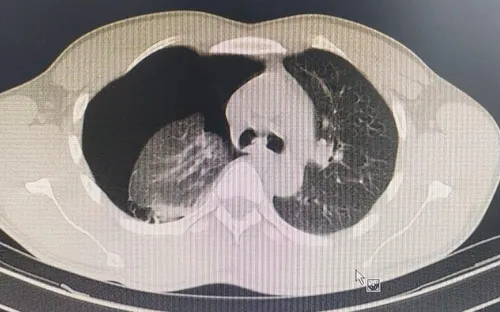

Vỡ kén khí gây tràn khí màng phổi khi chơi thể thao

14/09/2020

VTV.vn - Bệnh nhân nam, 36 tuổi, trú tại Long Biên, Hà Nội khi đang chơi thể thao bỗng có triệu chứng đau ngực, khó thở.